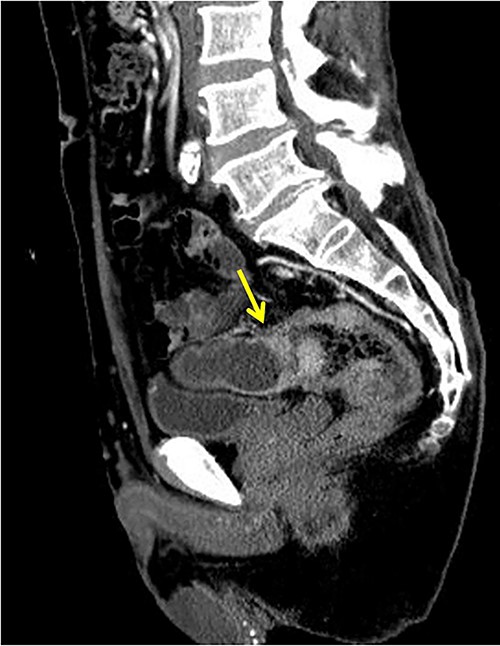

The patient was a 61-year-old woman presenting to our institution with the chief complaint of abdominal distension and diarrhea for a month. Colonoscopy showed descending colon cancer with all circumference-related stenosis. Her laboratory findings revealed a serum CEA level of 5.5 μg/ml and serum CA19-9 level of 778.4 U/ml. The CT scan results showed wall thickening in the descending colon. The descending colon on the proximal side of the tumor was dilated. The ileum is in contact with the tumor. Positron emission tomography (PET-CT) showed fluorodeoxyglucose (FDG) accumulation in the descending colon, mediastinal lymph nodes, enlarged mesenteric lymph nodes, and pararenal aortic lymph nodes (Fig. 3). The patient was preoperatively diagnosed as Stage IV, but she had obstructive symptoms, so surgery was planned. Laparotomy with left hemicolectomy and partial small bowel resection were performed. The ileum, including lymph node dissection around the fistula formation, was also resected.

Descending colon with circumference tumor and small intestine invasion.